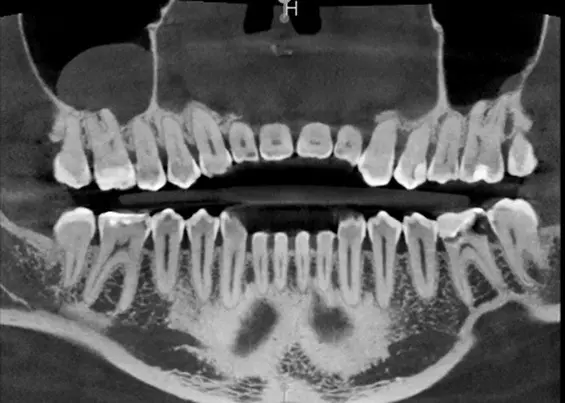

W tym wydaniu m.in: koferdam w adhezyjnych protokołach rekonstrukcyjnych, Low Dose – przełom w tomografii komputerowej CBCT, odpowiedzialność karna lekarza za błąd medyczny, wykorzystanie sonoabrazji w różnych dziedzinach stomatologii.